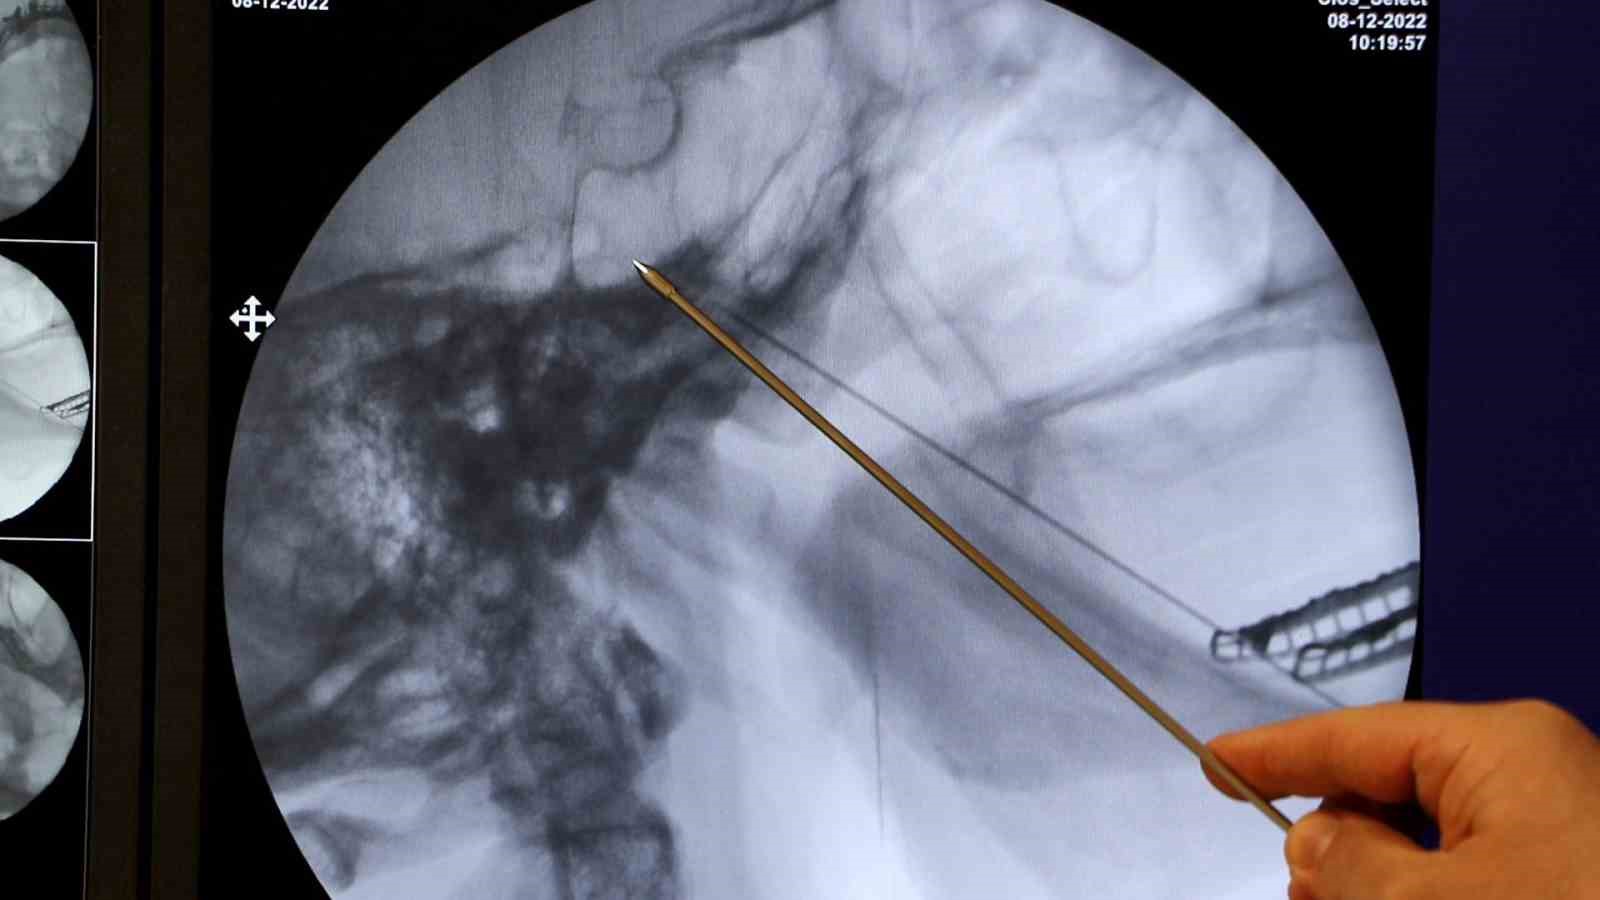

Trigeminal nevralji hastalığının tedavisi uygulayan az merkez olduğunu ve birçok hastanın bu nedenden dolayı hastanın böyle bir tedavinin olduğunu bilmeden kendilerine geldiklerini söyleyen Algoloji Uzmanı Dr. Öğretim Üyesi Mustafa Kurçaloğlu, “Bu hastalıkta, hastaların yüzünde sinirin trasesinde bulunan iz düşümünde saniyeler süren çok şiddetli elektrik çarpması gibi gelen birkaç saniye süren fakat gün içerisinde yüzlerce defa tekrar eden çok şiddetli ağrı atakları meydana geliyor. Özellikle hastaların yemek yemesiyle, konuşmasıyla, yüzlerini yıkamasıyla tetiklenen çok şiddetli bir ağrı ataklarıyla karakterize olan bir hastalıktır. Trigeminal nevraljinin hastaların esasında yarısında sebebi belli değildir. Kalan yarısında da trigeminal sinirin beyine girdiği yerde bir damarın sinirin köküne teması ağrıya sebep olabilir. Esasında çok nadir bir hastalık sayılmaz. 50 yaşın üzerinde hastalığın sıklığı artar. 50 yaş üzerinde yaklaşık 200’le 1 oranında hastalık görülür. Öncelikle ilaçla tedaviye başlıyoruz hastalarımızda. İlaç tedavisi ile fayda görmeyen, ağrısı azalmayan hastalarda bu sinirin uç dallarına enjeksiyonlar ya da radyo frekans tedavileri yapıyoruz. Ufak enjeksiyon işlemleriyle de fayda görmeyen hastalarda sinirin beyin sapına girdiği yerde kökünü bularak, radyo frekans dediğimiz özel bir iğne ile kontrollü lezyonla birlikte ısı enerjisi vererek yakım işlemi yaparak sinirdeki çakmaları engelliyoruz. Bu işlem hastaların yüzde 80-90’ında fayda etmektedir. Özellikle 2 yıllık takiple hastaların yüzde 80’inde hala işlemin etkisinin devam ettiğini gözlüyoruz. Birkaç sene sonra ağrıları tekrar ederse tekrar yapılabilen bir işlemdir. Bu işlem üst düzey teknik beceri gerektirmektedir. Çünkü iğneyi 1 santim fazla ilerletirsek beyin sapına da girmiş olabiliyorsunuz. Biz yılda yaklaşık 50 hastaya bu işlemi yapıyoruz. Maalesef hastalar ve hekimler tarafından çok bilinen bir yöntem değildir. Uygulayan merkez sayısı da çok az olduğu için hastaların çoğu böyle bir tedavinin olduğunu bilmeden bizlere geliyorlar. Fakat tedaviyi anlattıktan sonra kabul ediyorlar. Yıllarca çok şiddetli ağrı duyan, sosyal, iş, evlilik hayatlarında sekteye uğramış hastalar bizim tedavimizden sonra mutlu bir şekilde ayrılıyorlar. ‘Bu zamana kadar keşke bu işlemi yaptırsaydım. Bu kadar yıldır boş yere ağrı çekmiş olmazdım’ diyorlar” diye konuştu.